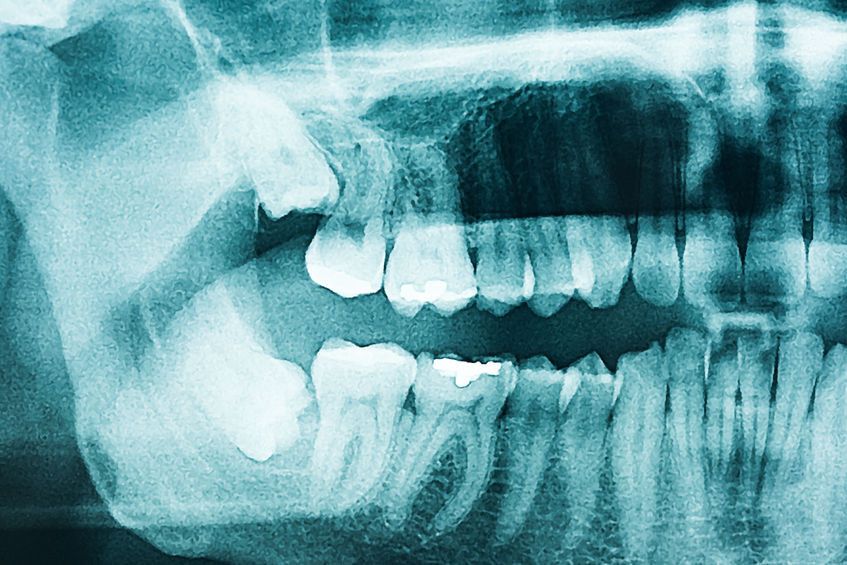

Faktanya, kepala dan wajah terdiri dari ribuan saraf serta otot-otot yang berfungsi untuk meneruskan rangsangan atau stimulasi seperti rasa sakit kepada otak dan sistem saraf pusat.

Pada hampir seluruh kasus sakit gigi disertai sakit kepala melibatkan saraf trigeminal. Maka, berdasarkan inilah sakit gigi termasuk penyebab langsung yang dapat memicu sakit kepala.

Impaksi Molar Tiga

Impaksi molar tiga adalah kondisi yang terjadi akibat gigi bungsu (molar) tidak memiliki cukup ruang untuk tumbuh.

Impaksi molar tiga menyebabkan gejala rasa sakit atau kaku pada rahang di bagian gigi yang mengalami keluhan. Apabila terdapat infeksi, penderita bisa mengalami sakit gigi sampai kepala.

Beberapa gangguan pada gigi dan rahang memang terbukti dapat memicu sakit kepala.

Keadaan ini karena persarafan pada daerah-daerah wajah dan kepala yang dicakup oleh saraf trigeminal saling terhubung, sehingga sakit gigi bisa disertai rasa sakit di kepala.